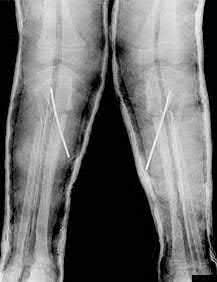

Question 19:

A 28-year-old male sustains a closed comminuted tibial shaft fracture. Two hours post-injury, he develops severe leg pain unyielding to narcotics. His blood pressure is 120/80 mmHg. Intracompartmental pressure monitoring is performed. Based on current guidelines, which measurement dictates an emergent 4-compartment fasciotomy?

Options:

- Absolute compartment pressure > 20 mmHg

- Absolute compartment pressure > 25 mmHg

- Delta pressure (Diastolic BP - Compartment Pressure) < 30 mmHg

- Delta pressure (Systolic BP - Compartment Pressure) < 30 mmHg

- Delta pressure (Mean Arterial Pressure - Compartment Pressure) < 40 mmHg

Correct Answer: Delta pressure (Diastolic BP - Compartment Pressure) < 30 mmHg

Explanation:

Acute compartment syndrome is classically defined by tissue hypoperfusion. The absolute compartment pressure is less reliable than the differential pressure (Delta P). A Delta P (Diastolic Blood Pressure minus Compartment Pressure) of less than 30 mmHg is an absolute indication for emergency fasciotomy, as capillary perfusion gradient is lost when tissue pressure approaches the diastolic pressure.